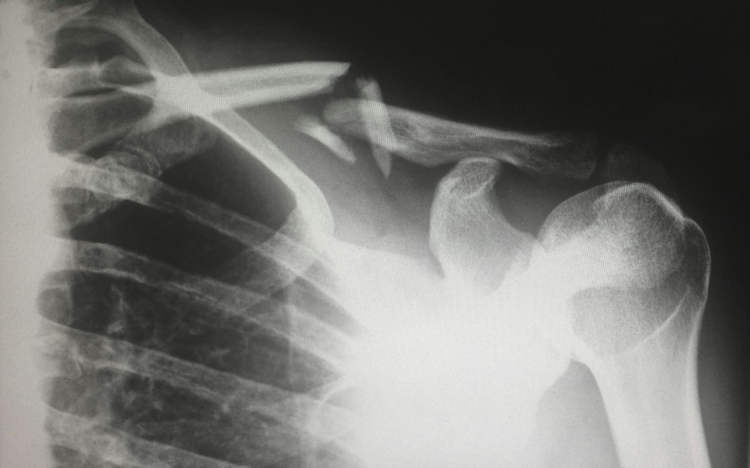

A Chinese woman with severe vitamin D deficiency caused by excessive sunscreen use suffered a bone fracture just by rolling in her bed.

Doctors at the XinDu Traditional Medicine Hospital, in Chengdu, China, recently reported the unusual case of a 48-year-old local woman who had apparently suffered a bone fracture just by casually rolling in bed. According to Dr. Long Shuang, tests performed at the hospital showed that the unnamed woman’s vitamin D levels were extremely low, which had accelerated bone loss and caused the onset of severe osteoporosis. Further investigation revealed that the patient had avoided sunlight since childhood, rarely wearing short-sleeved shirts and always applying sunscreen when going outside. Her case was presented as a warning for other sunscreen enthusiasts who might be overusing it and thus affecting their bone health.